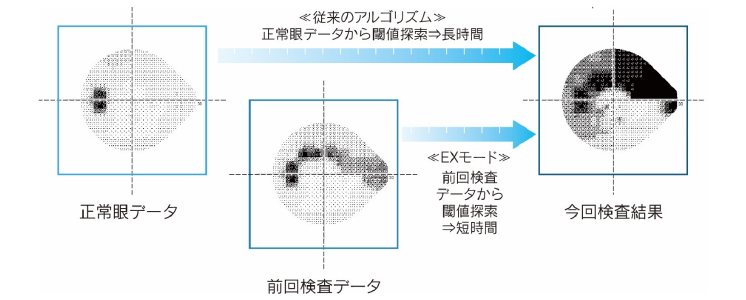

過去データを利用した時間短縮アルゴリズム「EXモード」

患者様個別の過去データを活用し、緑内障患者の長期経過観察データを参照することで、正確性の向上と検査時間の大幅な短縮を実現しました。過去データは「AIZE」、「AIZE-Rapid」のいずれのデータも使うことができ、EXモードは従来の検査設定と同様に「AIZE」と「AIZE-Rapid」をお選びいただけます。